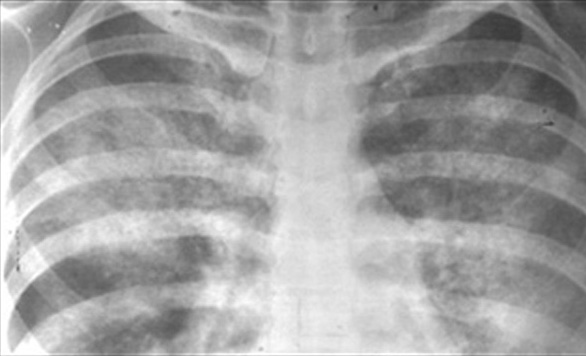

Alveolar form